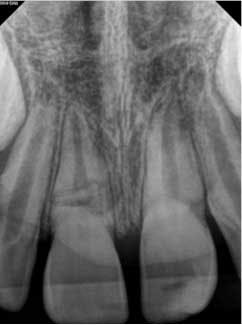

At three months, the clinical testing was equivalent and radiographs showed a fracture still present, but the periodontal ligament (PDL) and lamina dura (LD) were intact and uniform, especially near the fracture line (figure 2). At six months, there was no change in the response to vitality testing and radiographs continued to show no deleterious changes (figure 3).